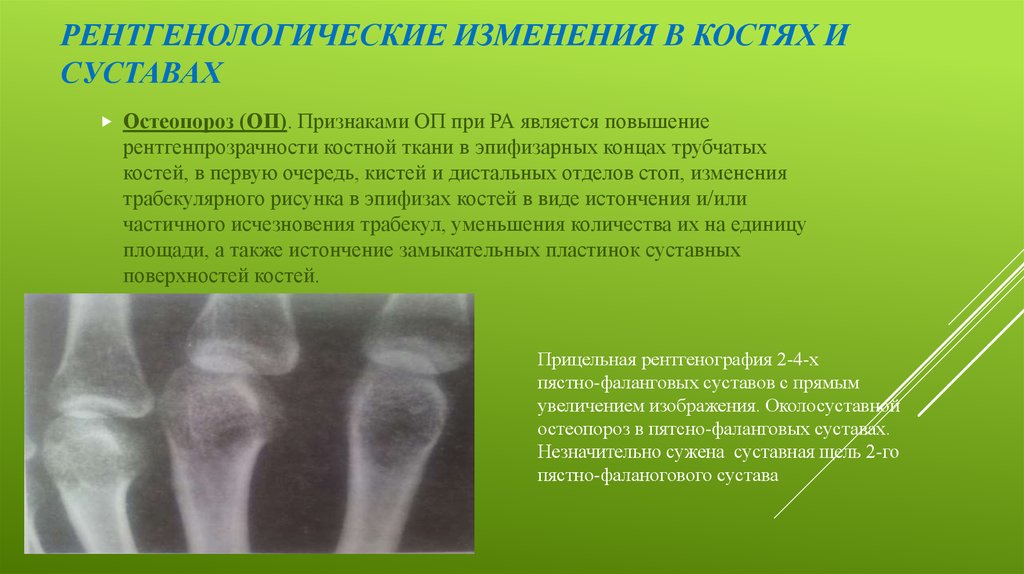

Медицинские снимки: рентген коленного сустава при остеопорозе